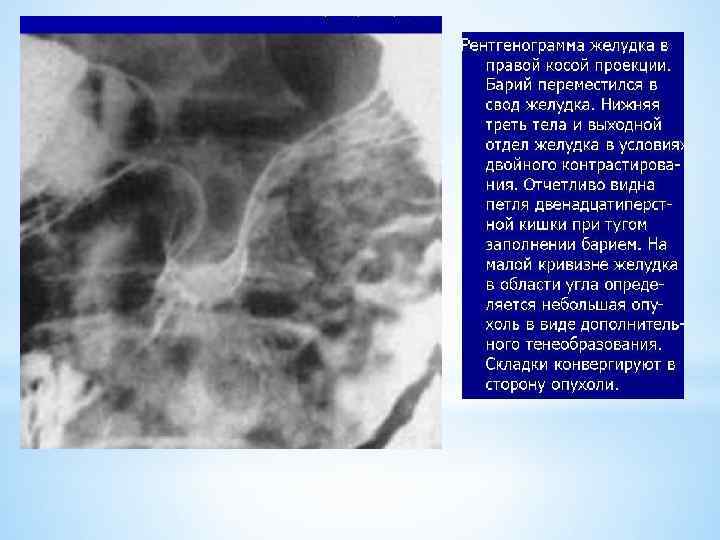

Исследование начинают с пищевода: - 1 -й глоток прослеживают стоя в прямой проекции от полости рта до желудка; 2 глоток - в правой косой проекции и проверяют смыкание кардии; в левой боковой проекции - контуры пищевода; затем больного укладывают на спину на. Исследование желудка: - пневморельеф антрального отдела (1 -й снимок); - больного кладут на живот и дают газообразующую смесь - уродан (1 ч. ложка) и 30 гр. воды; или 0, 5 ч. ложки лимонной кислоты, 0, 5 ч. ложки соды и 30 гр. воды; - больного опять кладут на спину - антральный отдел раздувается (2 -й снимок в прямой проекции 24 х 30); критерий раздувания желудка сохранение зубчатости по большой кривизне; - 3 -й снимок в правой косой проекции - лучше виден антральный отдел: по медиальному контуру задняя стенка у малой кривизны; по латеральному контуру - передняя стенка у большой кривизны;

- 4 -й снимок в левой косой проекции, желудок наслаивается на позвоночник, газ уходит в свод, антральный отдел скрыт за синусом: по медиальному контуру - передняя стенка у малой кривизны; по латеральному контуру - задняя стенка у большой кривизны; - 5 -й снимок - стоя в прямой проекции - газ смещается в свод; - 6 -й снимок - стоя в левой боковой проекции - тело и луковица двенадцатиперстной кишки.